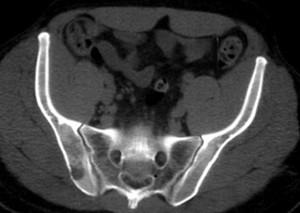

问题 女,38岁,腰背和右侧骶髂关节痛,请结合图像,选出最可能的诊断 ( )

选项 A、骨巨细胞瘤 B、骨髓瘤 C、类风湿关节炎 D、右髂骨结核 E、化脓性关节炎

答案 D